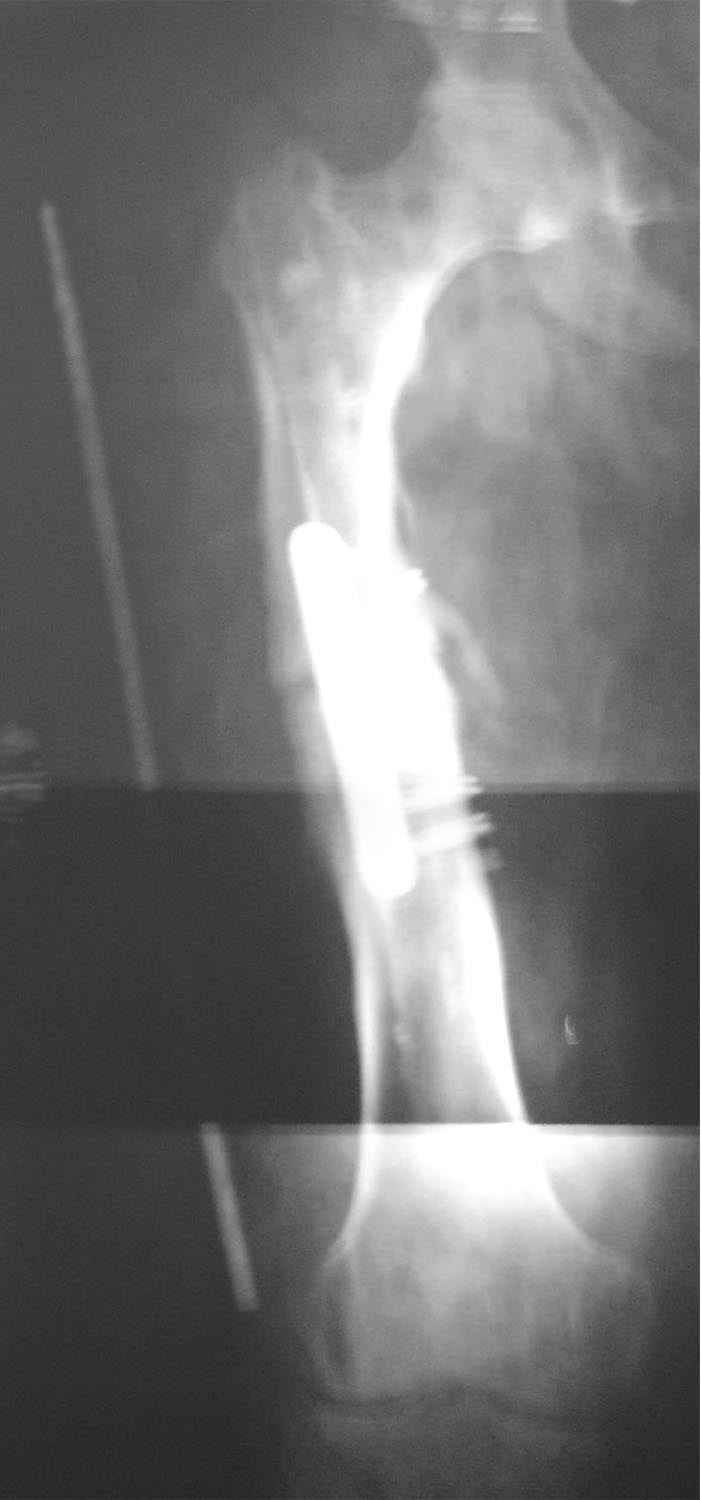

царицанский с 20 Декабрь 2006, 01:03

AC>По длине - уже "семь раз отмерили"? С длиной ве-таки как дело обстоит? И виден небольшой варус, надо бы и его устранить.

укорочение 15мм, клинически варуса нет. в приложении снимок на 2 пленках с центр на суставах, с приклеенной на уровне кости стержнем L-300mm,d-5mm.